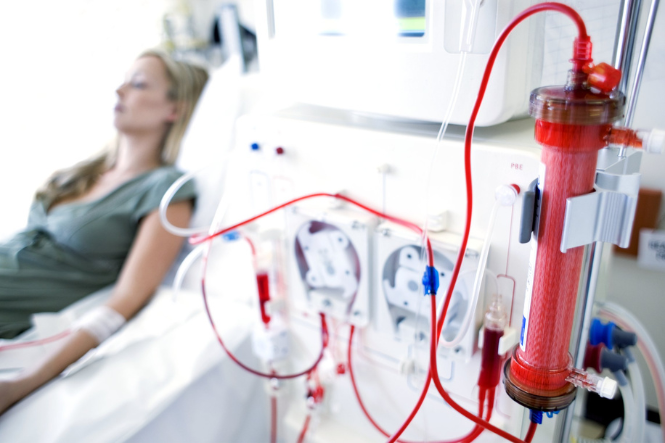

Your kidneys have a key role in your health. They filter and remove waste and excess fluid from your body. This means you need to take good care of them. Find out how to look after your kidneys, the signs they're not functioning well and more.